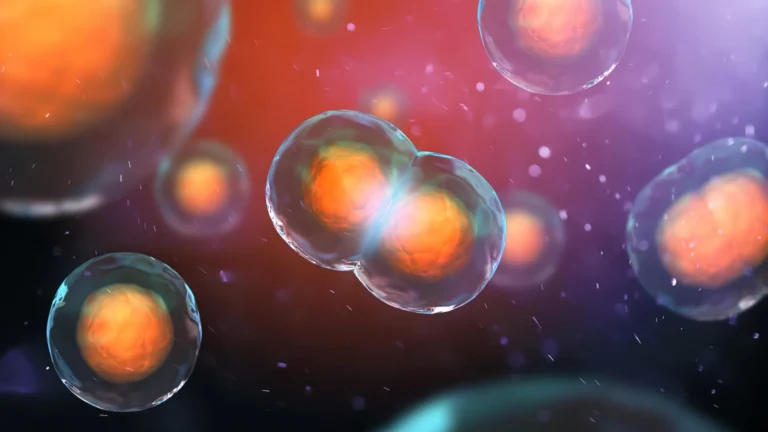

A cada segundo, inúmeras células no corpo humano se dividem para criar novas células. Este é um dos processos mais importantes na biologia e exige que milhares de moléculas trabalhem juntas com uma precisão incrível. Contudo, às vezes, esse processo apresenta falhas de maneiras inesperadas. Antes que uma célula possa se dividir em duas células…